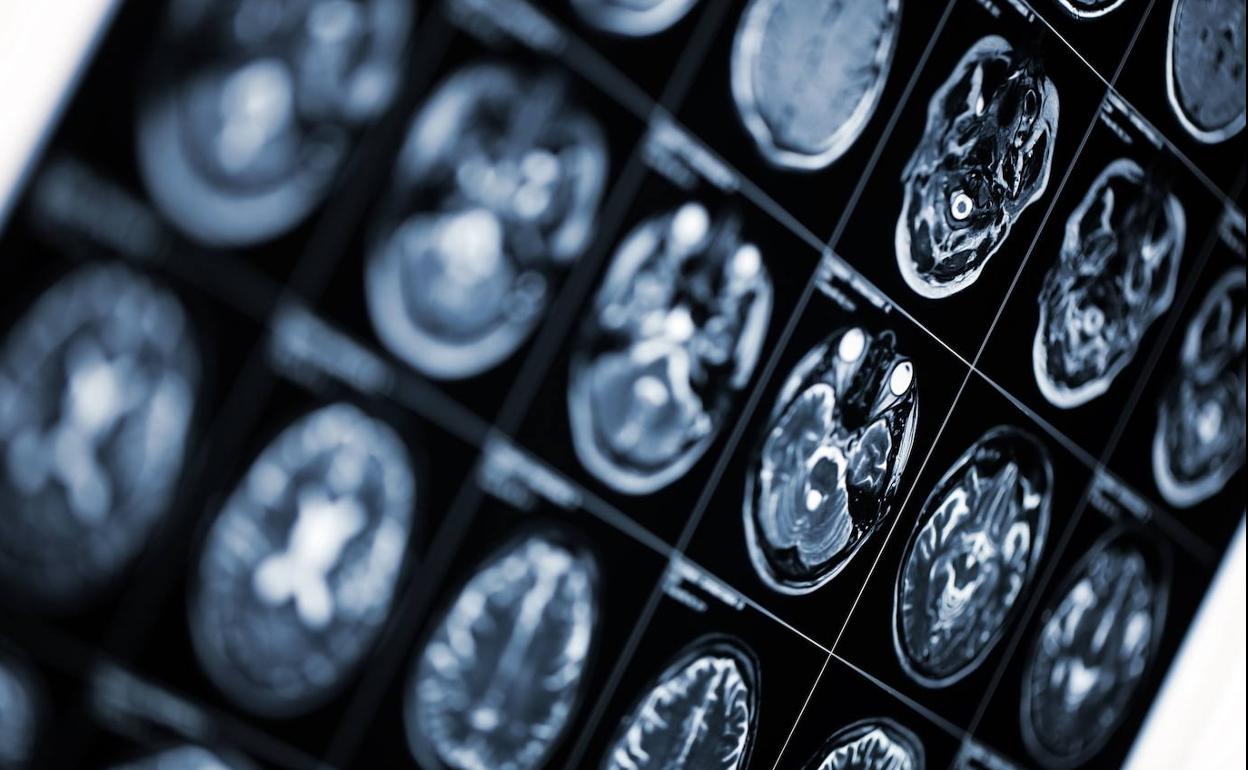

La estrategia 2019-2023, que no cuenta con una financiación específica, busca mejorar el diagnóstico precoz y la atención a los enfermos y los familiares que les cuidan

El Gobierno y las autonomías aprobaron este jueves el Plan Nacional de Alzhéimer y Otras Demencias a través de sus representantes en el Consejo Territorial de Servicios Sociales. Este plan, el primero de su clase en España, recoge los objetivos y las medias con las que se pretende aumentar el diagnóstico temprano de esta enfermedad, que padecen unos 800.000 españoles, y mejorar la atención integral a los afectados por la dolencia y a los cientos de miles de familiares que los cuidan.

El plan diseña la implantación de políticas preventivas contra la enfermedad y busca mejorar la capacidad de diagnóstico precoz que, en la actualidad, según los expertos, no alcanza a entre un 30% y un 40% de quienes ya padecen las primeras fases de la dolencia. Se trata de una enfermedad aún sin cura, pero sí hay tratamientos que lograr ralentizar o detener durante años la progresión del alzhéimer, por lo que detectarlo pronto puede mejorar de forma notable la salud y la calidad de vida del enfermo. Una de las medidas será formar a los profesionales sanitarios para que detecten pronto síntomas y signos que pueden alertar de la enfermedad. La estrategia nacional también fomentará la investigación sobre las causas, la prevención y el tratamiento de las demencias.